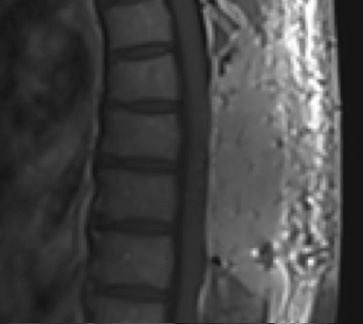

Postoperative MRI T1w demonstrating interval resection with cord re-expansion (blue arrow)

Postoperative MRI T2 illustrating the restoration of CSF surrounding the cord (blue arrow)

Pathology came back as Atypical Meningioma, WHO grade 2. Postoperative MRI showed a gross total resection without residual tumor, and appropriate spinal cord re-expansion. On her most recent follow-up at 6 weeks, she was very pleased with the results from the surgery. She reports resolution of her preoperative thoracic back and radicular pain, and great improvement with her ability to ambulate and overall function. It is demonstrated by her interval VAS of 2/10, and ODI of 23/100. She is expected to continue improving with time and therapy. Follow-up plan is to observe with radiographic surveillance.